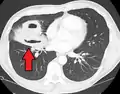

Pulmonary abscess on CT scan